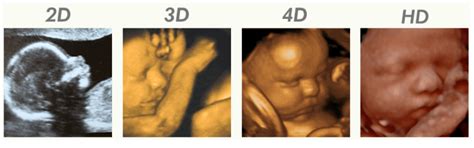

3D en 4D echo's

Een 3D echo plaatst 2D echobeelden achter elkaar om diepte te creëren. Een 4D echo is een live 3D echo, waarbij u uw kindje in bewegende 3D beelden kunt bewonderen. De nieuwste 4D echoapparatuur wordt gebruikt om uw kindje zo herkenbaar mogelijk in beeld te brengen.